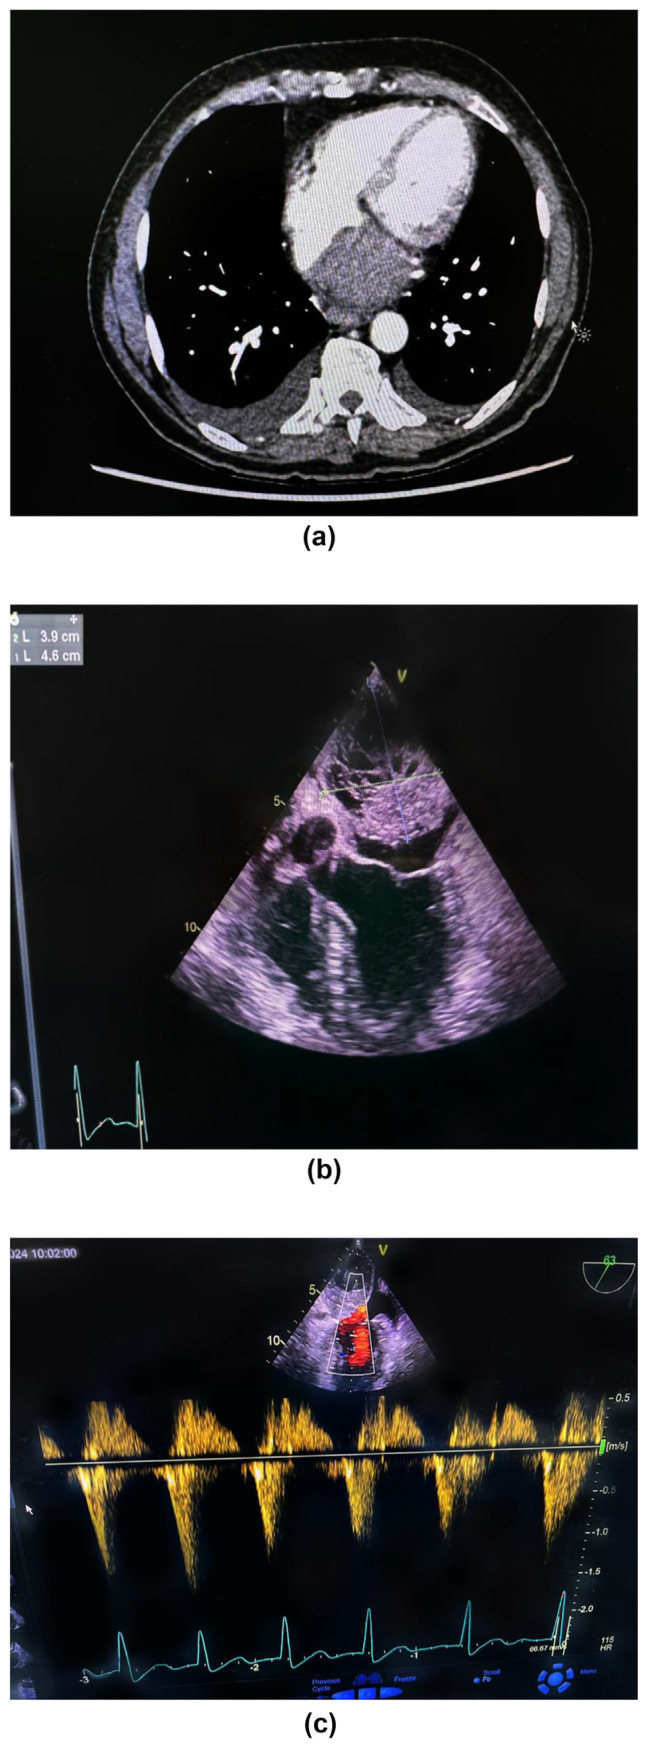

Spontaneous interatrial hematoma is a rare clinical entity leading to the obliteration of the left atrial cavity and causing haemodynamic compromise, necessitating immediate surgical intervention. Herein, we report a patient with acute chest pain with normal coronaries and echocardiographic evidence of left atrial mass. The investigations revealed the mass to be a thrombus rather than tumour. The patient underwent surgery to remove a large thrombus completely enclosed within the interatrial septum. The septum was then repaired using a pericardial patch. No apparent etiological factor was found. Spontaneous atrial wall dissection should be considered in the differential diagnosis of acute chest pain.